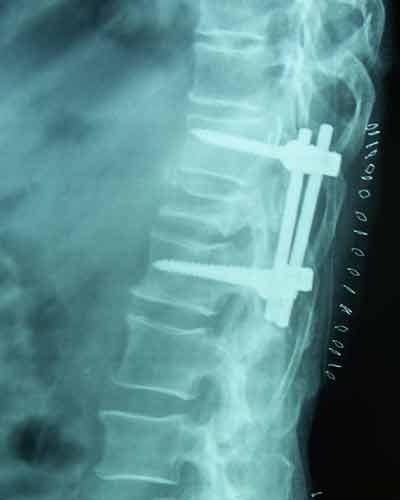

Post-op Lateral

60 years old female with one& half months old fracture L1 presented with complete paraplegia with bladder & bowel involvement. She was treated with posterior decompression (Laminectomy), reduction of retroplused fragrant & pedicure screw fixation. Full neurological recovery on 6th day.

Case:1 Traumatic Fracture L1 with Cauda Equina